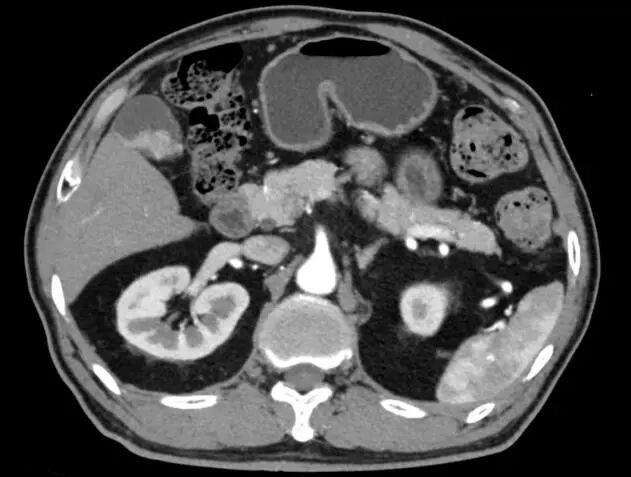

此次接受手术的患者张先生(化名),因右上腹持续性疼痛前往我院东院区就诊,经彩超检查提示胆囊占位性病变,进一步完善腹部增强CT检查后,提示胆囊癌。面对这一棘手病情,余昌中教授团队迅速行动,结合影像学检查、肿瘤标志物检测等结果,组织院内多学科会诊,认真严谨评估患者肿瘤分期及心肺功能,制定了适合该患者的个体化的胆囊癌根治术方案,团队严格执行围手术期管理要求,明确了手术切除范围、淋巴结清扫规范及术中应急处理预案,为手术成功奠定了坚实基础。